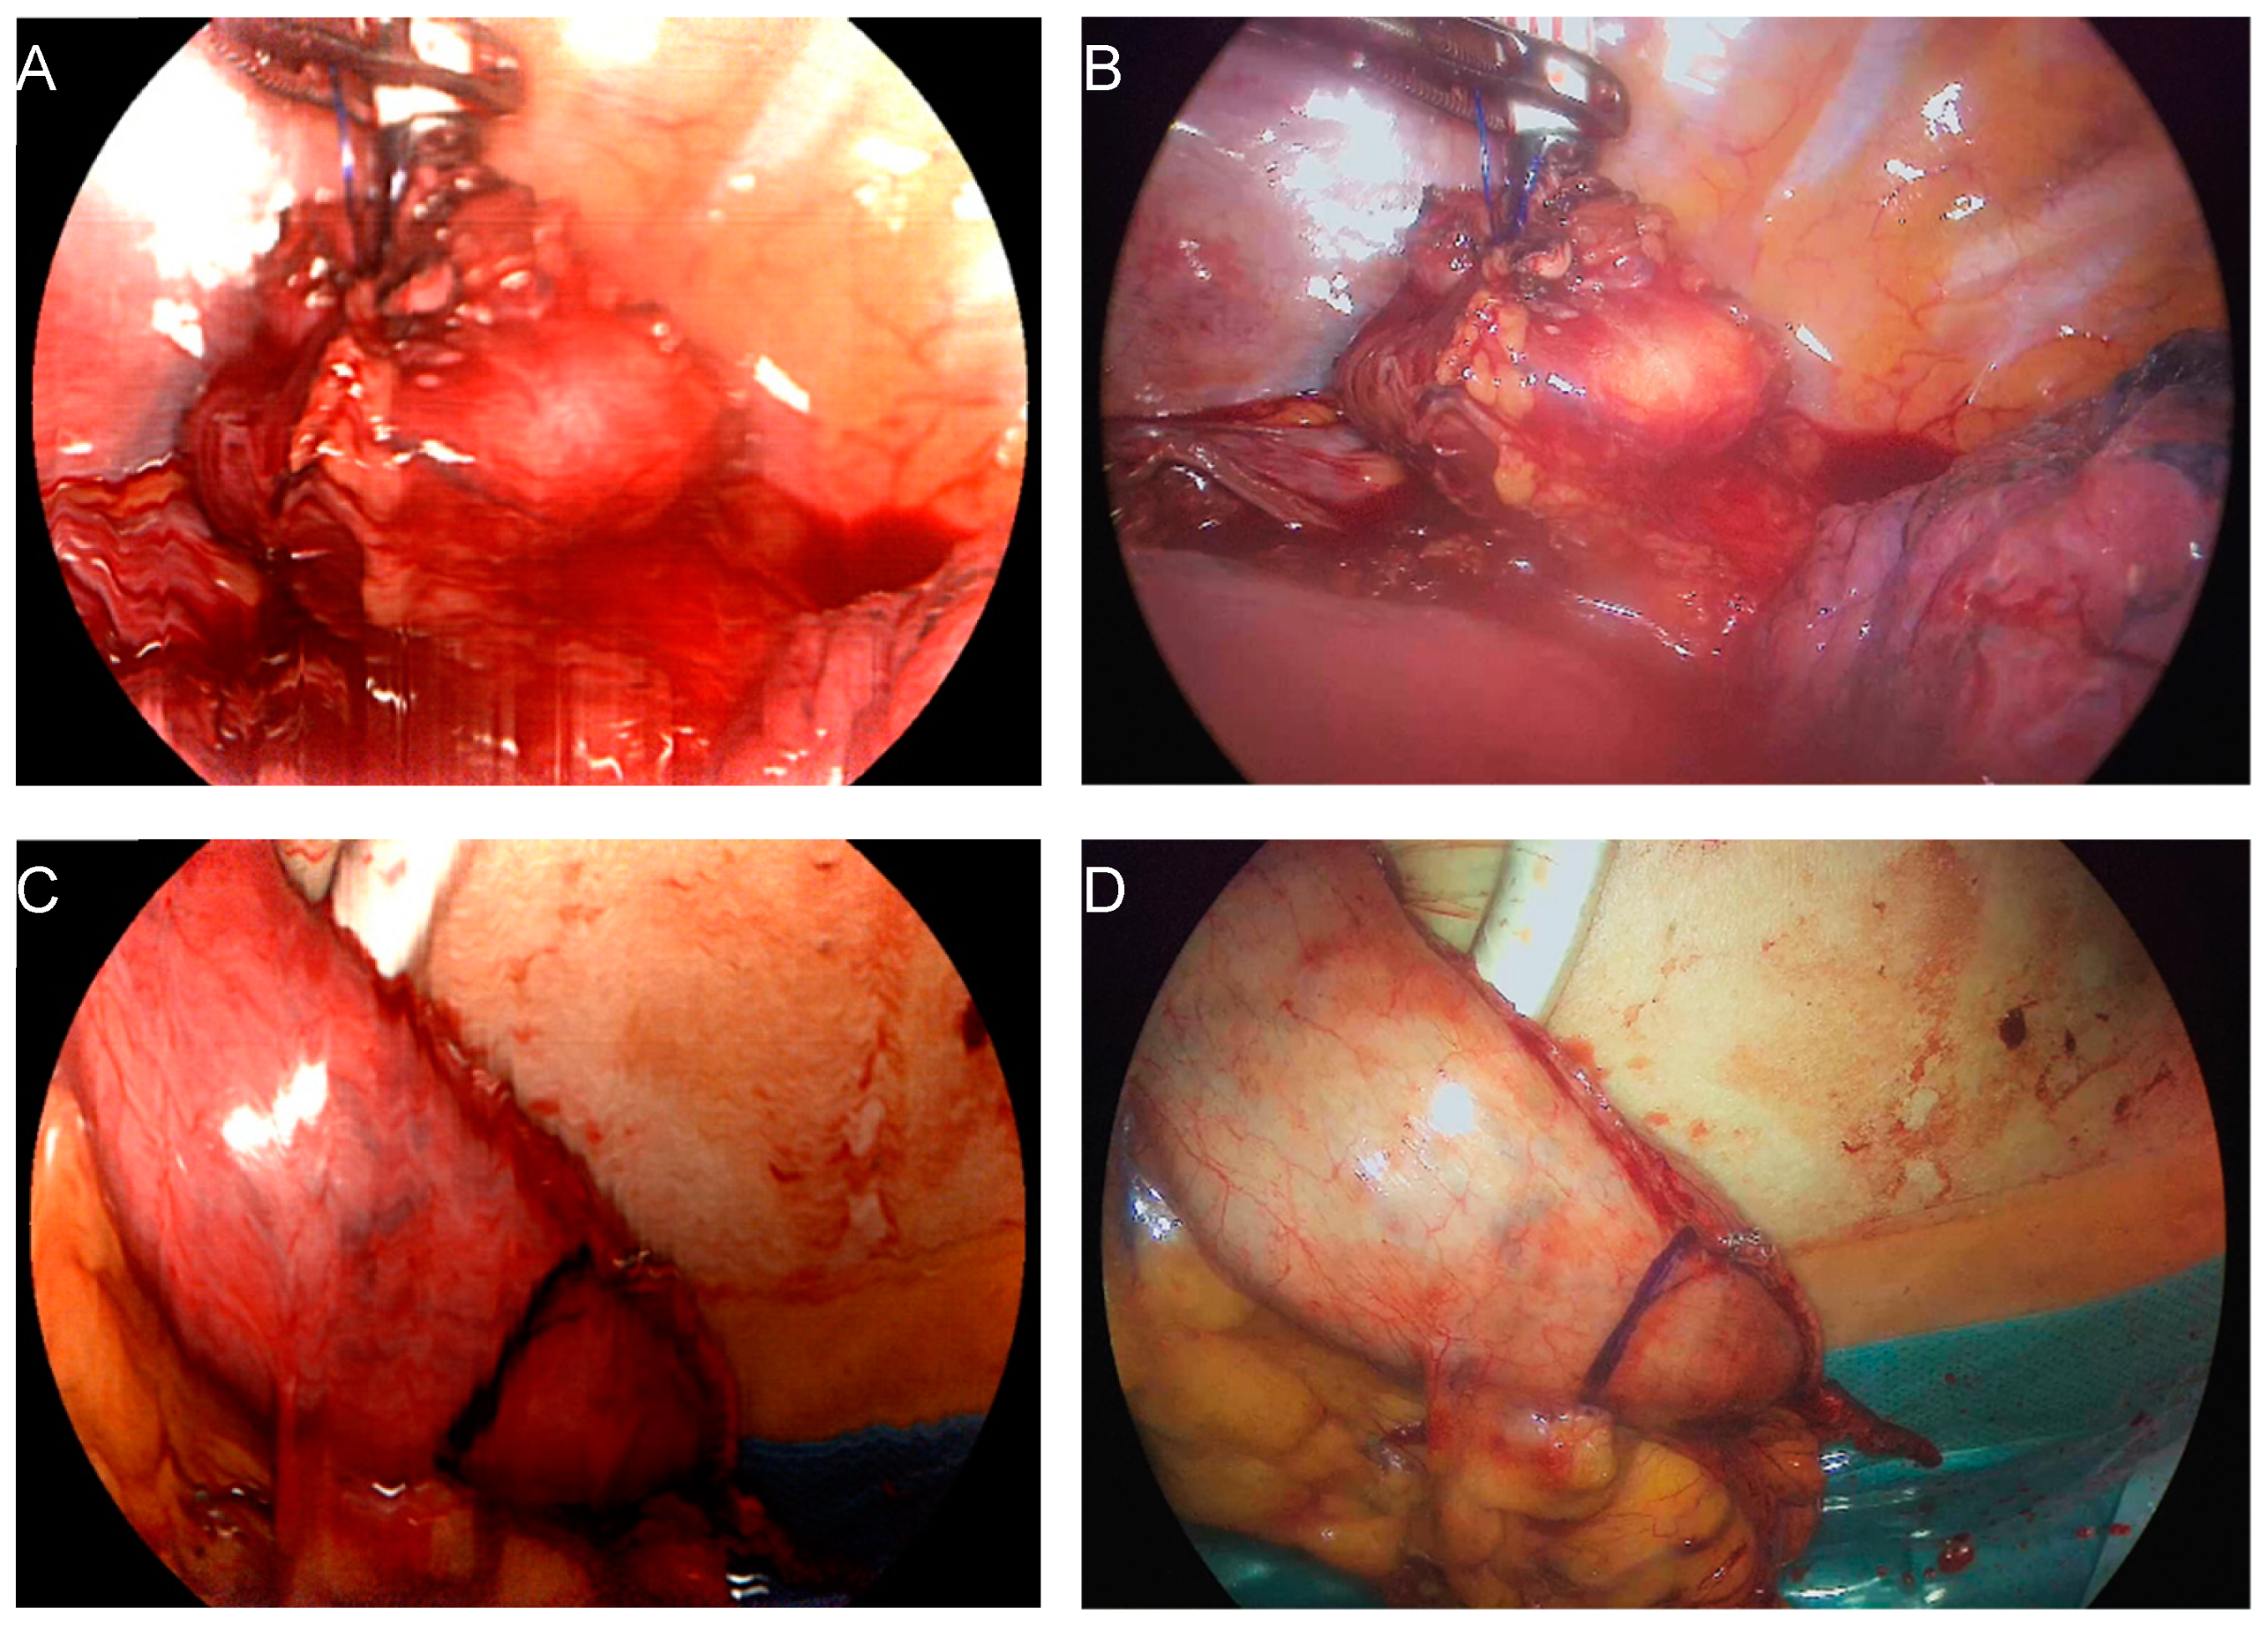

2.2. Surgical Procedure and Hyperspectral Imaging

3.2. Comparison of Intraoperative Perfusion Imaging of the Gastroesophageal Sites (Group 1)

3.3. Perfusion Evaluation of the Gastric Conduit by HSI-MIS (Group 1) and HSI-Open (Group 2)